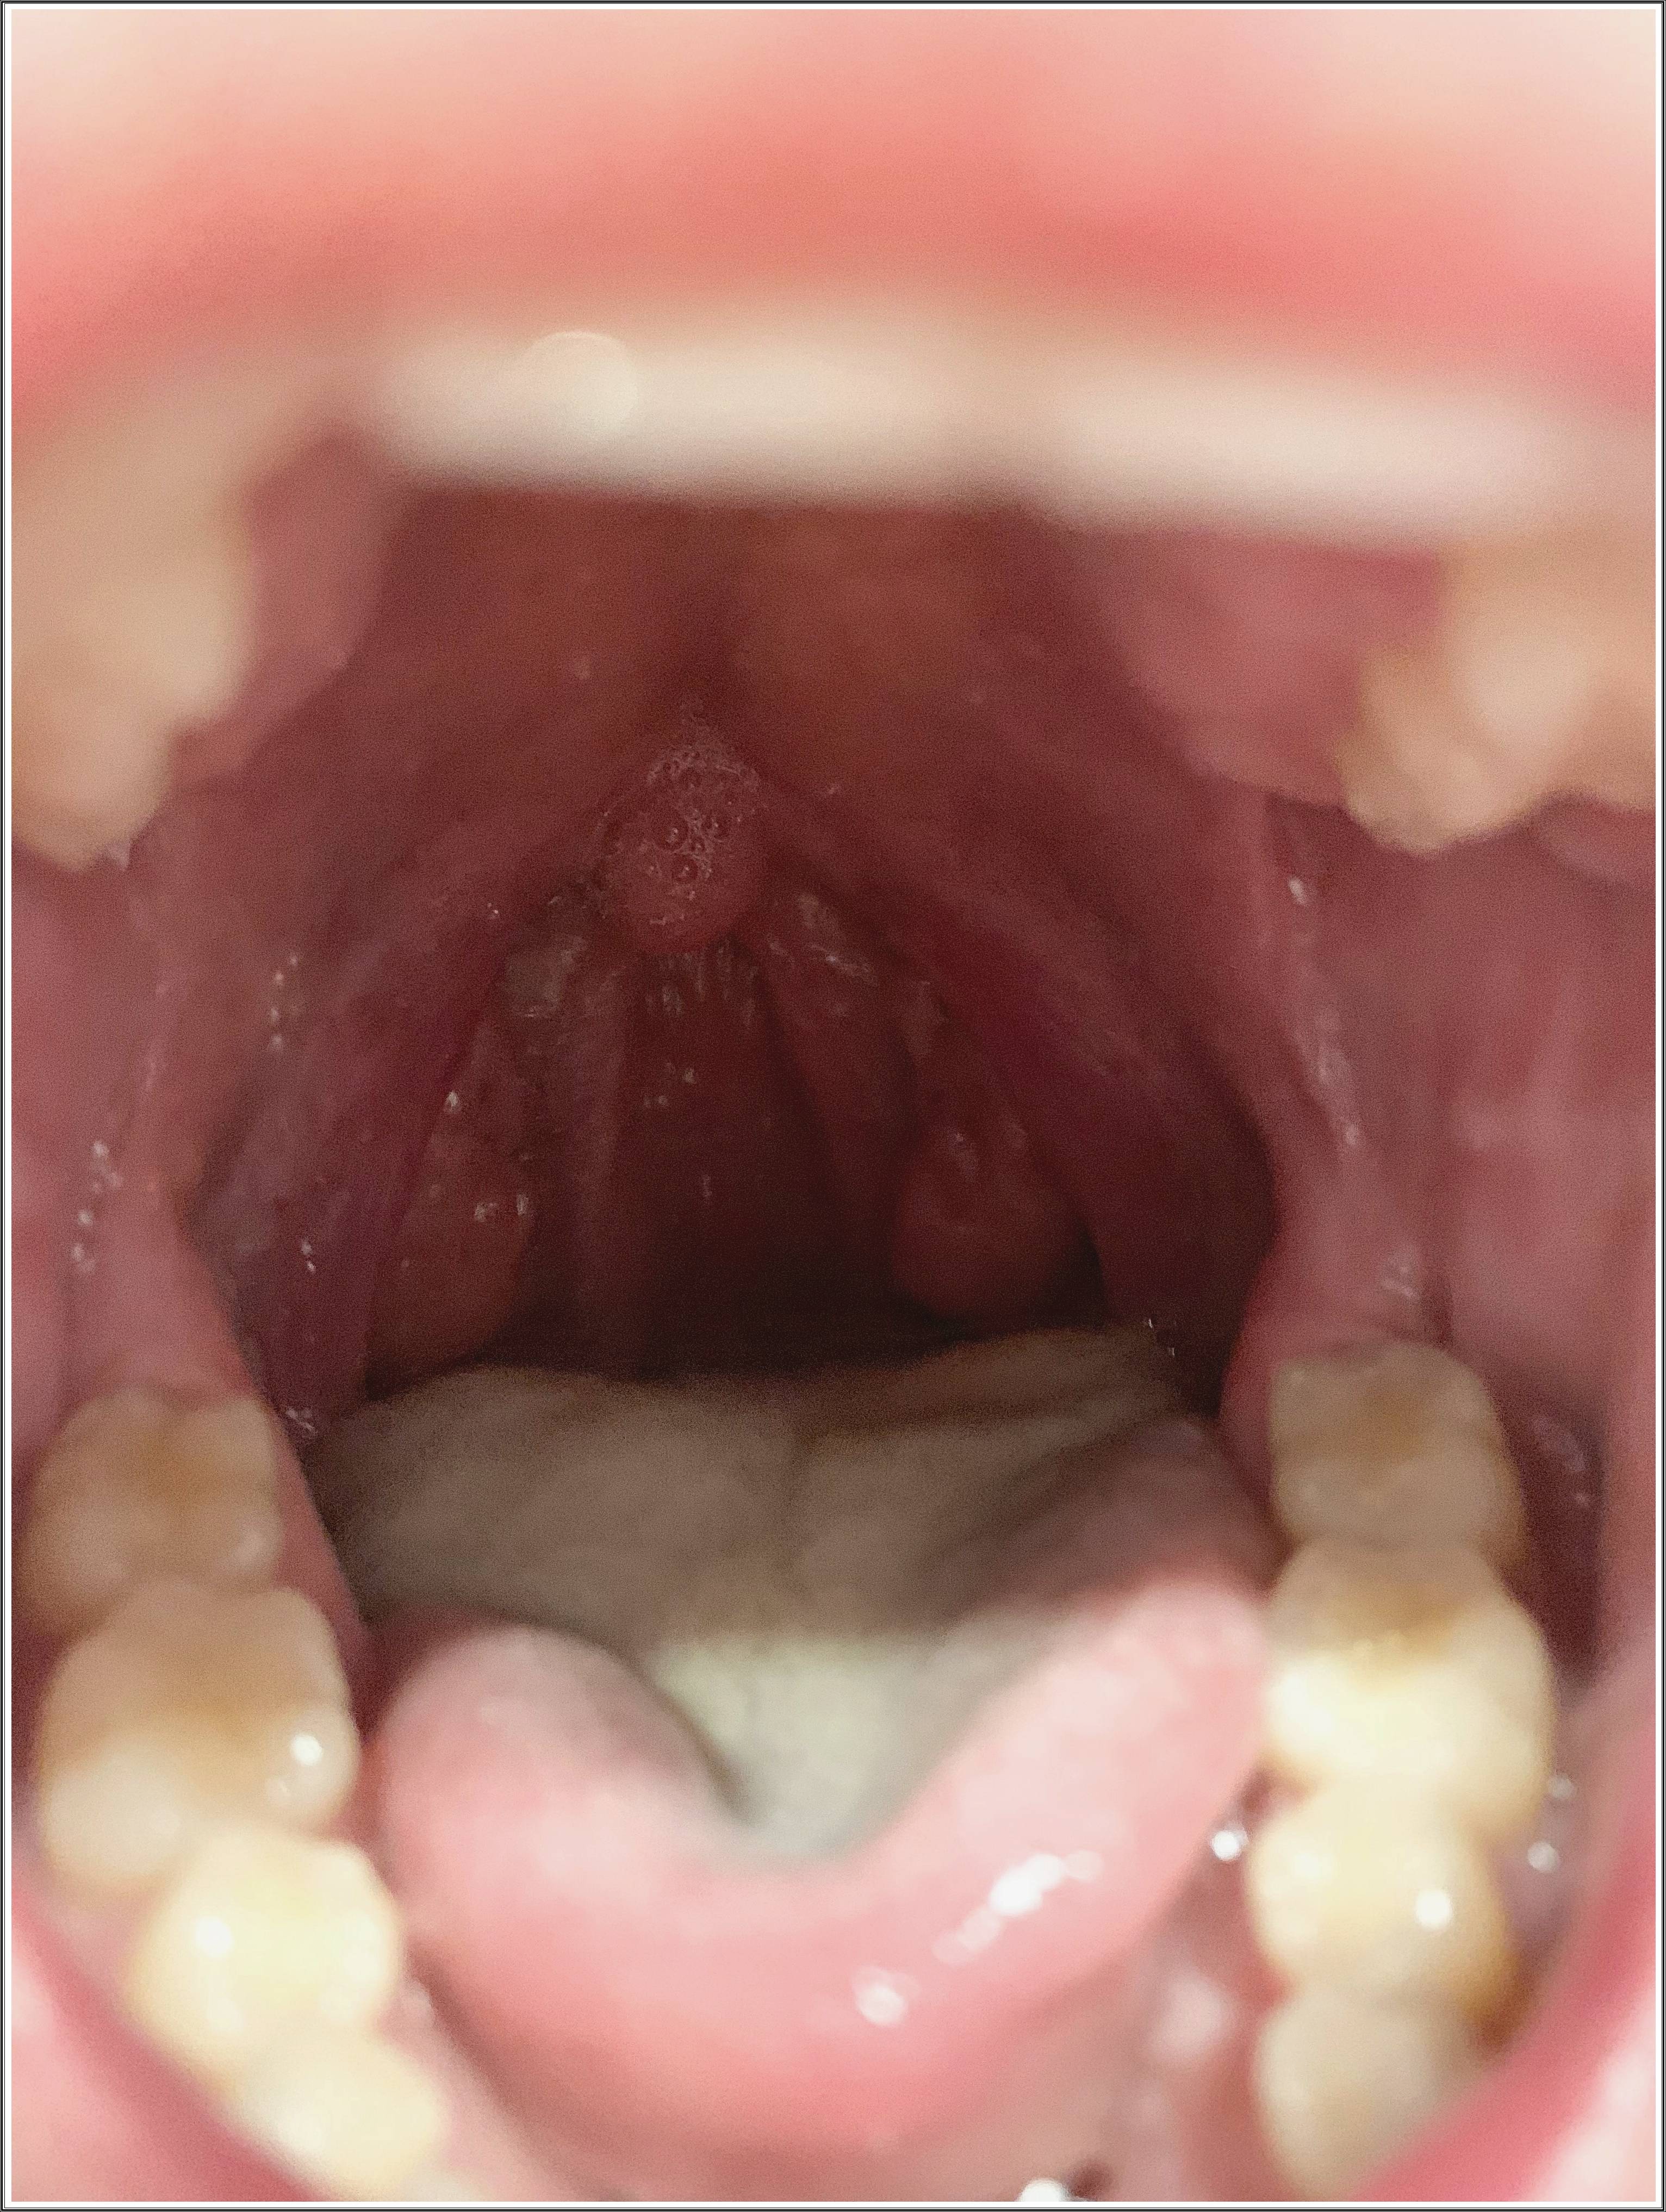

편도결석(tonsillolith)은 편도선의 틈새에 음식물 찌꺼기, 점액, 죽은 세포 등이 쌓여 굳어진 덩어리입니다.

흰색 또는 노란빛을 띠며, 크기는 좁쌀 정도에서 콩알만 한 크기까지 다양합니다.

음식이 목에 닿을 때 찌릿한 느낌이 든다. - 편도 표면에 흰색 점이 보인다

거울과 손전등으로 확인 시 작은 알갱이가 보인다. - 잦은 편도염

밝은 조명에서 혀를 최대한 내밀고 “아~” 소리를 내면서 목 깊숙이 확인합니다.

편도 표면에 작은 흰색 알갱이나 덩어리가 보이면 결석일 가능성이 큽니다. - 혀압자나 면봉 사용